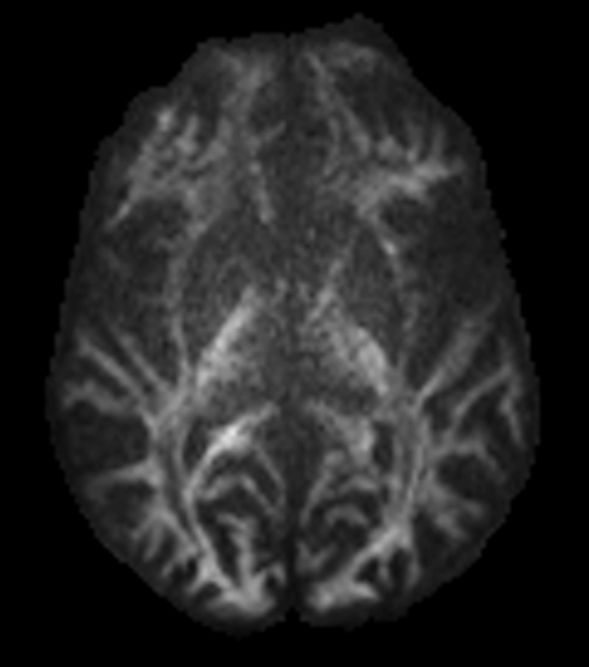

DWI b1000 (coronal reformat)

-